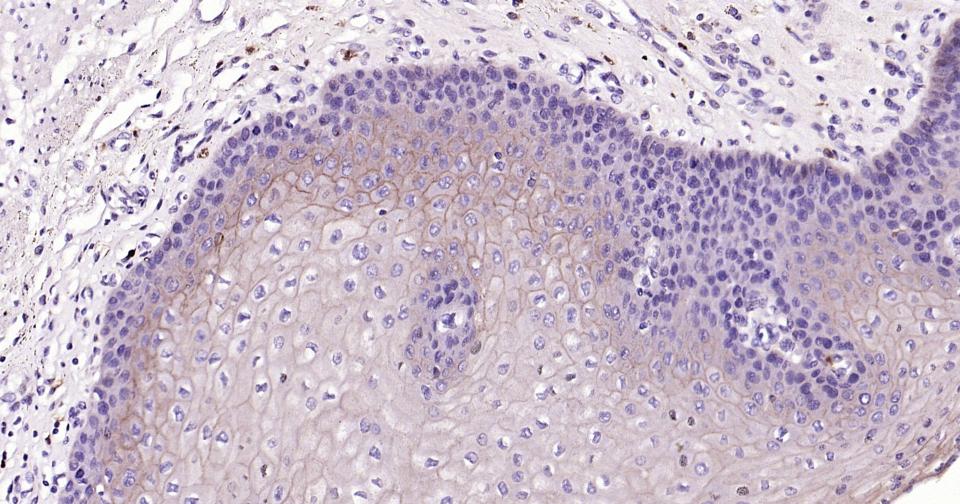

Paraformaldehyde-fixed, paraffin embedded Human Abdominal skin; Antigen retrieval by boiling in sodium citrate buffer (pH6.0) for 15 min; Antibody incubation with E cadherin Monoclonal Antibody, Unconjugated(bsm-60814R) at 1:200 overnight at 4°C, followed by conjugation to the bs-0295G-HRP and DAB (C-0010) staining.